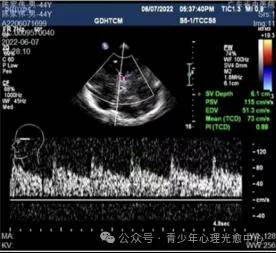

根据广东省中医院影像中心的多普勒影像显示:

抑郁焦虑存在共性,即脑部严重缺氧,大脑血流量、流速严重不足。